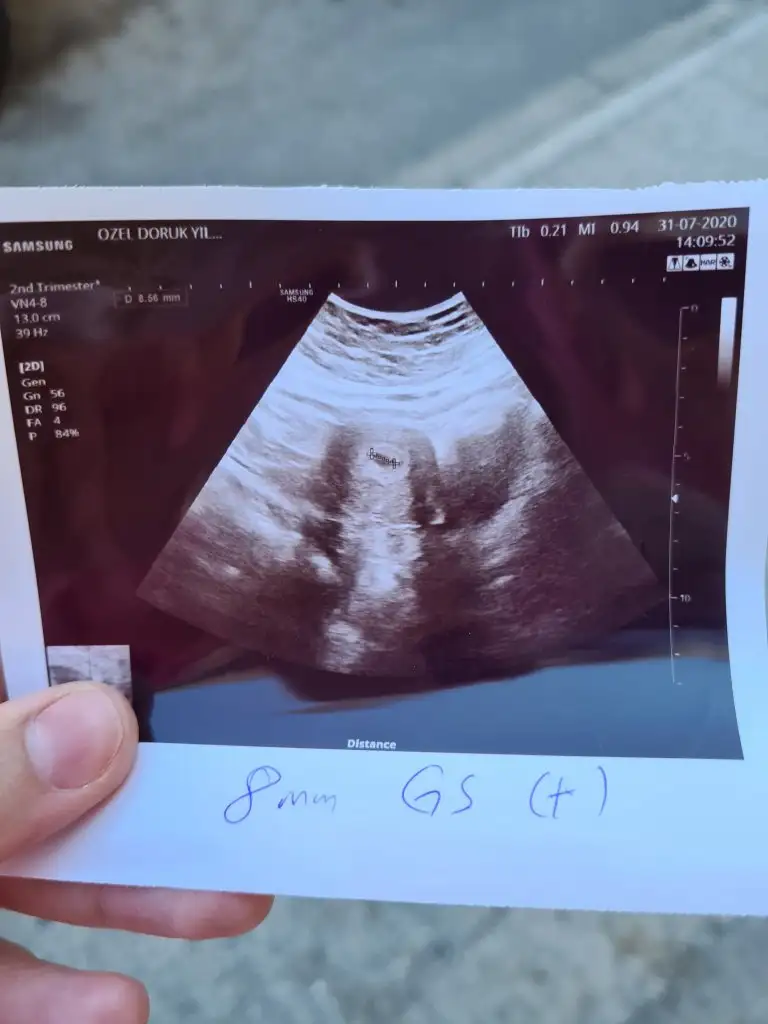

Evet sendede çizgi var içindeCanım bak buda benim 5+2 bebek gözükmüyor ama yolk kesesi gözüküyor demişti gittiğimiz doktor özel bi hastanenin nöbetçi kadın doğumuna gitmiştim iyi düşün iyi olsun inşallah canım belki doktor seninde yolk kesesini kastetmiştir. Bebeği ilk haftalarda besleyen kese o.

Benim 30 temmuzda 402 Di.Bu gün doktora gittim beta falan bakmadı kese göründü 4 haftalık dedi net konuşmasa da. yani sizin değr de güzel değere takılmayın inşallah sağlıcakla ilerler gebeliğimizKızlar 4 haftalık beta değeriniz kaçtı? Herkesin ve her hamileliğin durumu farklı biliyorum ama önceki gebeleiklerimin neden sonlandığını gösteren bir beta tablosu var karşımda.zaten olumlu olsun diye nasıl beklemişim işte umut demek ki... ilk kaybımda 2019 da ayın 20 Veya 22 si adet günüm. 28 inde betam 747 4 gün sonra 1725 4 gün sonra 3121 2 şer kat artmamış... 2.ci de de adet günğmden bir gün sonra 27 2 gün sonra 110 adetten 10 gün sonra 1170 çok dengesiz olmuş.bugün mecbur kaldım lekelenmeden sonra beta baktırdım.tahminen adet günümdeyim 493 çıktı.bir de pazar günü baktıracağım inşallah.değer nasıl şu an ?

İnşallah canım.artış önemli.50 ile başlayıp doğuma giden de çok.ben öncekilerin düzensizliğini artış olmadığını anlatmaya çalıştım aslında kuzum.inşallah sağlıkla ilerler bakalım bekleyip göreceğizBenim 30 temmuzda 402 Di.Bu gün doktora gittim beta falan bakmadı kese göründü 4 haftalık dedi net konuşmasa da. yani sizin değr de güzel değere takılmayın inşallah sağlıcakla ilerler gebeliğimiz